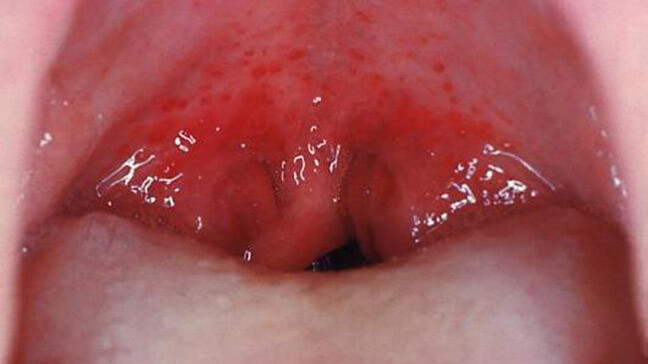

What Causes Red Spots On The Roof Of Your Mouth?

Red spots on the roof of your mouth can be caused by a variety of different reasons. Some are just a minor inconvenience, while others could be a sign of a more serious health issue that may require further investigation. Here are some common possibilities:

Coxsackievirus

The virus behind hand, foot and mouth disease, coxsackievirus can cause painful blisters and red spots on the roof of the mouth, as well as on the hands and feet. It is most common in children under five years of age, but does occur in people of all ages. Treatment options include over-the-counter medications for fever and pain, as well as special medicated mouthwashes to help alleviate the discomfort associated with the oral sores.

In rare cases, oral sores or lesions can be a sign of oral cancer, so it is important to have any spots that are painful, cause difficulty in eating or drinking or do not heal quickly checked by your dentist.